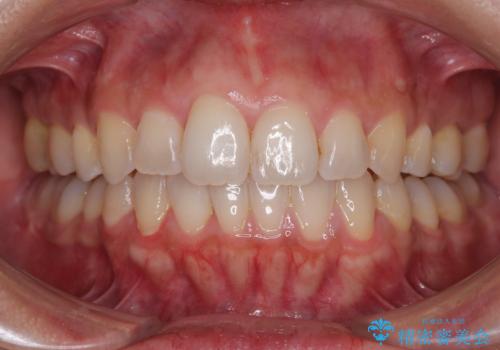

前歯のデコボコを改善 インビザラインの矯正治療

- 前歯のデコボコを治したいとのことで来院された患者様です。

上下顎ともに歯列全体の後方移動とIPR(歯と歯の間を削る)によってデコボコが解消するように設計し、インビザラインにより治療を行うこととしました。

下顎前歯は後戻りを起こしやすいため、舌側を細いワイヤーで固定し、マウスピース型リテーナーで保定を行うこととしました。